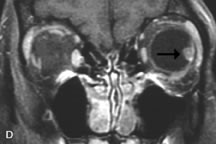

PATIENT PREPARATION Before MRI is performed, patients must be screened and prepared to avoid the potential hazards associated with the strong magnetic field. Patients who have ferrous aneurysm clips or cardiac pacemakers, who depend on life-support equipment, or who retain a possible metallic intraocular foreign body are not candidates for this imaging modality. MRI cannot be performed on obese patients who cannot fit into the bore of the magnet. Patients who are claustrophobic may not tolerate a prolonged period of study within the confines of the magnet, whereas others might do well if given a mild sedative. All worn metallic objects (e.g., necklaces, watches) should be taken off, credit cards set aside, and eye makeup removed before entering the room containing the magnet.5,20,34,35,36 NORMAL ORBITAL ANATOMY T1-weighted images provide the best anatomic details of the orbit because they display superior contrast resolution between normal structures (see Fig. 8). The vitreous has a long T1, resulting in an intermediate signal similar to brain, whereas the crystalline lens and sclera appear dark because of a longer T1 and short T2. The extraocular muscles, like all skeletal muscles, demonstrate a moderately long T1 and short T2 and highly contrast with the intense signal of the surrounding orbital fat (adipose tissue has an extremely short T1). The lacrimal glands appear as mottled areas of reduced intensity of the signal from the orbital fat in the lacrimal fossa. The optic nerves are seen with the same signal intensity as brain white matter and are hypointense relative to the orbital fat because their Tl is longer than the Tl of fat but shorter than the Tl of water. Cortical bone is not well delineated because it contains little free water, yielding minimal signal in MRI, and thus appears dark on all pulse sequences. This feature explains why MR images of the orbital apex and intracanalicular portion of the optic nerves are superior to comparable CT scans. Partial volume averaging of the bones in these regions obscures soft tissue details on CT images, whereas MRI reveals the signals only from the soft tissue structures with no cortical bone input. Bone marrow, on the other hand, is seen as a relatively intense signal because of its high fat content (see Fig. 8).37,38 T2-weighted pulse sequences are not ideal for imaging normal anatomy; however, they are particularly useful in revealing pathologic conditions (see Fig. 9). T2-weighted studies are most easily recognized by a bright vitreous signal. ORBITAL DISEASES Vascular Lesions Cavernous hemangiomas appear as well-circumscribed, smooth, usually intraconal masses that are isointense to muscle on T1-weighted images and hyperintense on T2-weighted images (Fig. 12). Patchy early enhancement is typically followed by diffuse, more homogeneous enhancement.39 The internal architecture of the mass, including septation and internal vasculature, may often be appreciated with high-quality orbital imaging.40 Lymphangiomas consist of ectatic vascular channels within a connective tissue stoma with varying degrees of lymphoid cellularity. On MRI, these tumors are typically poorly circumscribed, multicompartmental, and heterogeneous, often showing cystic dilations with fluid levels (Fig. 13). The signal characteristics within lymphangiomas vary considerably, reflecting cystic and solid components and the varying paramagnetic characteristics of blood at different stages of degradation.40–42 Acute hemorrhage appears hypointense on both T1- and T2-weighted formats. Methemoglobin present in subacute hemorrhage (3 to 14 days) leads to hyperintense signal on both T1- and T2-weighted images.41 A small percentage of lymphangiomas appear radiologically indistinct from orbital cavernous hemangiomas.43 Orbital varices are venous malformations that expand with increased systemic venous pressure, such as with Valsalva maneuvers. Because rapid acquisition of images during a Valsalva maneuver is important in imaging such a lesion, conventional or spiral CT is currently the modality of choice.44 MRI is an excellent modality for demonstrating enlargement of the cavernous sinus and dilation of the superior ophthalmic vein in patients with high-flow carotid-cavernous fistulas (Fig. 14).37MRA may be helpful in the evaluation of the venous outflow pattern. The rapidly flowing blood in these vascular structures carries the excited protons out of the section before they can be imaged, resulting in their dark appearance.5 In low-flow dural arteriovenous malformations, MRA may help define the arterial feeding vessels.45 Neural Lesions MRI is more effective than CT in delineating the intracranial optic nerves, chiasm, and optic tracts and, for this reason, is the preferred imaging modality in the evaluation of optic nerve disorders. The spatial relationships and image contrast of the orbital tissues with intraorbital optic nerve tumors is comparable between the two imaging modalities. The normal nerve is isointense to brain and appears enlarged and kinked owing to infiltration of an optic nerve glioma on T1-weighted images. Gliomas appear hyperintense on T2-weighted images and may be heterogeneous owing to cystic areas within the tumor. Contrast enhancement is variable.46 Intraorbital and intracranial optic nerve sheath meningiomas are usually isointense to cortical gray matter on Tl-weighted images and remain isointense on proton density studies (Fig. 15). Gd-DTPA is useful in delineating the intracranial extension of optic nerve meningiomas.7,47 The hyperostosis of bone and calcification associated with meningiomas are not demonstrated as well on MRI studies as on CT scans.20,37 Gd-DTPA–enhanced MRI also appears promising in the study of the permeability of the blood–brain barrier in selected optic neuropathies.22,48 MRI may reveal an enlarged optic nerve and some degree of contrast enhancement in cases of optic neuritis.49 Muscle Disorders Extraocular muscle enlargement in patients with thyroid-associated orbitopathy is demonstrated equally well with CT and MRI studies. However, the superior tissue contrast on MR images reveals better details of the relationships of the optic nerve to the thickened muscles at the orbital apex (Fig. 16).50 In addition, MRI may be able to differentiate between muscles that are enlarged as a result of edema and active inflammation and those enlarged because of fibrosis by their T2 relaxation times.21 Quantitative MRI was not found to be accurate in predicting the success of low-dose orbital irradiation.51 However, a muscular index relating the diameters of the rectus muscles to the bony orbital dimensions was useful in predicting optic nerve compression.52 MRI is also effective in imaging orbital tumors of mesenchymal origin, such as rhabdomyosarcoma, particularly in the assessment of extension into the anterior and middle cranial fossae (Fig. 17).37 The lack of any pathognomonic radiologic features necessitates rapid orbital biopsy when rhabdomyosarcoma is suspected. Osseous Lesions In general, CT is the imaging modality of choice when details of quantity and quality of bone are needed; however, abnormalities of bones can be detected indirectly by MRI. Cortical bone appears black (signal void) on MR images because of its low proton density and free-water content. The absence or discontinuity of the signal void of the orbital walls may represent bony destruction or fracture. Hyperostosis associated with prostate metastases or meningioma is visualized as areas of black smudging.50,53 Diseases in which the bone is replaced by pathologic tissues with a high free-water content, such as fibrous dysplasia, are well demonstrated on MRI. An intermediate signal intensity on T1-weighted images and hypointense signal on T2-weighted images is representative of fibrous dysplasia. Enhancement on post–Gd-DTPA MR scans is seen and is more evident in areas that are less mineralized.54 Cystic Lesions Dermoid cysts appear as rounded, well-defined lesions typically contiguous with an orbital bony suture. The high-intensity signal on T1-weighted images is attributed to the sebaceous-produced lipid contents (Fig. 18).31,50 Mucoceles may demonstrate a hypointense or hyperintense signal on MR images, depending on the concentration of proteinaceous or inflammatory fluid components. The integrity of the bony walls of the expanded sinus cavities cannot be assessed on MR as well as by CT.37,50,55,56 A high-signal intensity on Tl- and T2-weighted images is characteristic of orbital chronic hematic cysts because of the blood-breakdown products within the cysts.57 Trauma Although soft tissue relationships are usually better demonstrated on MRI, the evaluation of craniofacial bony trauma is preferable with CT. For example, prolapse of orbital fat through a fracture site and hemorrhage of adjacent tissues are demonstrated in an MR image, but the actual fractured bone is not imaged. Three-dimensional MRI of the orbit in subacute trauma has been described,58 although its precise role is not currently established. MRI has been suggested to be superior to CT in detecting intraorbital wooden foreign bodies.59,60 In a series of penetrating orbital injuries with organic foreign bodies, however, MRI was able to identify the foreign body in only four of seven cases.61 With an in vitro model for wood foreign body, McGuckin and colleagues concluded that CT was the imaging modality of choice.62 A careful history and, in selected cases, plain films to rule out a metallic foreign body are crucial before MRI is considered in patients with periocular trauma. MRI is particularly helpful in the detection and characterization of subperiosteal hematomas of the orbit (Fig. 19). They are most commonly seen in the subperiosteal space of the superior orbit as well-defined masses following a traumatic injury. The signal intensity varies depending on the acute, subacute, or chronic nature of the hematoma, based on the stage of blood degradation. Fresh hemorrhages are hypointense on T1-weighted images and hyperintense on T2 images. Hematomas that are 1 to 7 days old are hypointense on both T1- and T2-weighted images. T1-weighted images of hematomas more than a week old are hyperintense due to the oxidation of deoxyhemoglobin to methemoglobin, whereas the T2 images remain hypointense.63 Metastatic Tumors Breast carcinoma metastatic to the orbit has been demonstrated to be hypointense to the surrounding orbital fat on T1-weighted studies and hyperintense on T2-weighted images and has an affinity to the extraocular muscles (Fig. 20).50,64 The MRI characteristics of prostate carcinoma metastatic to the orbit have been described as involving the greater and lesser wing of the sphenoid, orbital roof, and optic canal. Diffuse bone hypertrophy with isointense or slightly hyperintense tissue on T1-weighted images represents the osteoblastic carcinomatous bone infiltration. Contrast enhancement is variable on T1-weighted and fat-suppressed images.65 Most other metastatic tumors also have a lower intensity signal on T1-weighted images and appear to displace or infiltrate normal orbital structures; however, their signal characteristics are variable on T2-weighted MR images.66 Many metastatic tumors demonstrate bright contrast enhancement with Gd-DTPA. Infectious Disorders MRI findings of preseptal and orbital cellulitis typically include increased signal intensities on T2-weighted images of the eyelids and orbital fat, respectively, due to the increased water content of the tissues. Since most cases of bacterial orbital cellulitis are associated with paranasal sinusitis, hyperintense signals of the affected sinuses may also be found on T2-weighted images as well as enhancement of polyps and granulation tissue on postgadolinium T1-weighted MR images. Subperiosteal abscess formation may occur due to contiguous spread of infection from the paranasal sinuses and appear on MRI as an area of intermediate signal on T1-weighted and proton-weighted MR images. The abscess may appear slightly hyperintense compared with muscle on T2-weighted scans with the necrotic contents having the greatest intensity.67 MRI and MRV are more sensitive than CT in revealing cavernous sinus thrombosis. Engorgement of the cavernous sinus, extraocular muscles, and ophthalmic veins is seen with hyperintensity of the thrombosed sinuses evident on all pulse sequences. The enlarged, thrombosed superior ophthalmic vein appears less hypointense than the normal contralateral ophthalmic vein, and hyperintensity within the lumen of the vessel may be seen on T1- and T2-weighted MR images.68 Inflammatory and Lymphoproliferative Lesions Inflammatory conditions of the orbit, both idiopathic (inflammatory pseudotumor) and those of known causes, have been found to be hypointense to fat and isointense to muscle on Tl-weighted studies and isointense or slightly hyperintense to fat on T2-weighted images (Fig. 21).50,64,69 The more fibrous or sclerosing varieties have less signal intensity on T2-weighted images. Marked enhancement is seen in pseudotumor infiltrates after gadolinium administration.70 The same signal characteristics are demonstrated in patients with Tolosa-Hunt syndrome, with mass lesions seen in the cavernous sinuses and orbital apices.71 Lymphomas have MRI characteristics similar to those of inflammatory lesions in that they are hypointense to fat and isointense to muscle on T1-weighted images (Fig. 22). They may appear hyperintense to fat on T2-weighted images, perhaps owing to less fibrosis than that seen in orbital inflammatory pseudotumor, although this is not a consistent finding.31,50,66 Lymphoid tumors typically enhance moderately after contrast injection. Unfortunately, studies have shown that tumor density and homogeneity are similar between inflammatory and malignant orbital infiltrates, and MRI cannot differentiate these lesions.72,73 Lacrimal Gland Tumors Lacrimal gland lesions present special problems in diagnosis and management. Pleomorphic adenoma (benign mixed tumor) should not be biopsied, but rather excised in toto. On the other hand, for lymphoma and inflammatory infiltrates, incisional biopsy is more appropriate than complete excision of the lacrimal gland. Thus, preoperative clinical and radiologic evaluation are especially crucial in planning appropriate surgical management. Pleomorphic adenomas demonstrate long T1 and T2 signal characteristics. They may show heterogeneity on T2-weighted images74 and moderate to marked enhancement with contrast.75 Signal characteristics of adenoid cystic carcinoma include hypointensity to fat on T1-weighted images, hyperintensity to fat with increased T2 weighting, and isointensity to fat on proton density-weighted studies (Fig. 23).31,75 Secondary bony alterations of the lacrimal fossa associated with lacrimal gland tumors, such as remodeling (benign mixed tumor) or destruction (adenoid cystic carcinoma), are seen indirectly on MR images; however, bone windows on CT scans provide better delineation of these changes. In contrast to the round or globular appearance of benign or malignant epithelial tumors of the lacrimal gland, lymphoproliferative tumors usually appear to be molding or draping onto the globe and the surrounding bony orbit. LACRIMAL DRAINAGE SYSTEM DISORDERS MRI with surface coils provides excellent spatial resolution and tissue-specific signal intensities of the lacrimal drainage system. These parameters have been found useful to more accurately demonstrate the extent of lesions in the lacrimal sac and differentiate long-standing mucoceles from solid tumors than CT.76 Physiologic studies in patients with tearing disorders now include MR dacryocystography, in which Gd-DTPA is either placed topically in the conjunctival fornix or injected by cannulation into the lacrimal sac. They provide a detailed morphologic and functional analysis of the lacrimal excretory system; however, they are no more sensitive than digital-subtraction dacryocystography or CT dacryocystography.77–79 INTRAOCULAR TUMORS On MRI, uveal melanomas have a typical appearance that helps to differentiate them from other primary and secondary intraocular tumors as well as choroidal detachments. Pigmented melanomas are hyperintense on Tl-weighted images, hypointense on T2-weighted studies, and hyperintense on proton density–weighted examinations (Fig. 24).30,31,50,80–82 These signal characteristics have been attributed to the paramagnetic properties of melanin because of stable free radicals that shorten the T1 and T2 relaxation times. Moderate enhancement is seen on postgadolinium T2-weighted images. Gadolinium-enhanced T1-weighted images are particularly sensitive in detecting choroidal melanomas.83 MRI may be less sensitive in detecting extrascleral extension of tumor than echography performed by an experienced ultrasonographer.84 Tumors metastatic to the choroid are hyperintense on T1- and T2-weighted images.24 The signal characteristics, however, may be similar to those seen with choroidal melanoma. Choroidal hemangiomas, on the other hand, have an intermediate signal on T1-weighted sequences and become hyperintense on T2-weighted images50 as well as proton density–weighted images.81 Retinoblastomas display moderate signal intensity on T1-weighted studies and a low signal on T2-weighted images.31,80,85 Calcification can be easily detected by CT and ocular ultrasonography but is not imaged by MRI.25,50 The presence of optic nerve involvement is best evaluated by MRI. ACQUIRED ANOPHTHALMIA When an eye is removed owing to tumor or trauma, an implant is typically placed in the intraconal space. MRI may be useful in defining the size, shape, and position of such orbital implants.86 Porous hydroxyapatite or polyethylene implants are preferred by many surgeons performing enucleation or evisceration. A porous implant offers the possibility of supporting a motility coupling peg to increase the movement of the overlying prosthesis. MRI with contrast is used by some surgeons to evaluate the degree of fibrovascular ingrowth in hydroxyapatite87 and porous polyethylene88 implants prior to motility peg placement. |